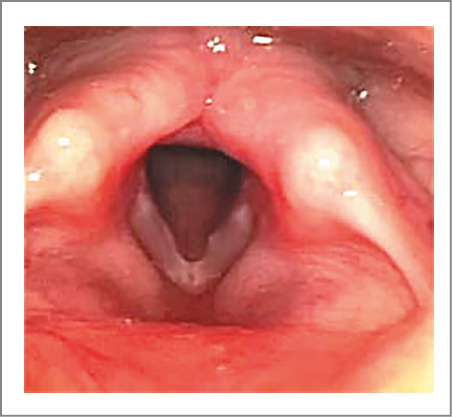

Дисхрония черпаловидных хрящей известна как один из вариантов ларингомаляции. Девять (11%) детей обратились с жалобами на дисфонию, которая появилась при увеличении голосовой нагрузки: дополнительных занятиях хором или вокалом, смене педагога по вокалу и репертуара, который оказался неудобен для исполнения. Следует отметить, что никто из пациентов и их родителей не предъявлял жалобы на нарушение дыхания как в период раннего детского возраста, так и на момент осмотра. У всех пациентов выявлен аритеноидный тип ларингомаляции.

Клиническая картина гортани выглядела следующим образом. В момент вдоха черпаловидные хрящи смещались латерально. Одновременно с этим верхушки черпаловидных хрящей и клиновидные хрящи западали в просвет гортани. Во время фонации они совершали незначительную экскурсию вверх и вновь западали при дыхании, т.е. наблюдался их коллапс. Этот симптом мы назвали «пляска черпаловидных хрящей» [5]. Один из вариантов дисхронии черпаловидных хрящей представлен на рис. 4.

Рис. 4. Мальчик Р., 9 лет. Дисхрония черпаловидных хрящей (ларингомаляция 2-го типа), узелки голосовых складок: а – дыхание; b – фонация.

Следует отметить, что в группе детей с дисхронией у 6 (7%) пациентов выявлены узелки голосовых складок, а у 3 (4%) – проявления физиологической мутации, т.е. сниженный тонус голосовых складок.